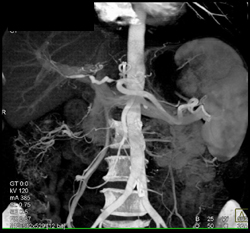

Ductus Aneurysm